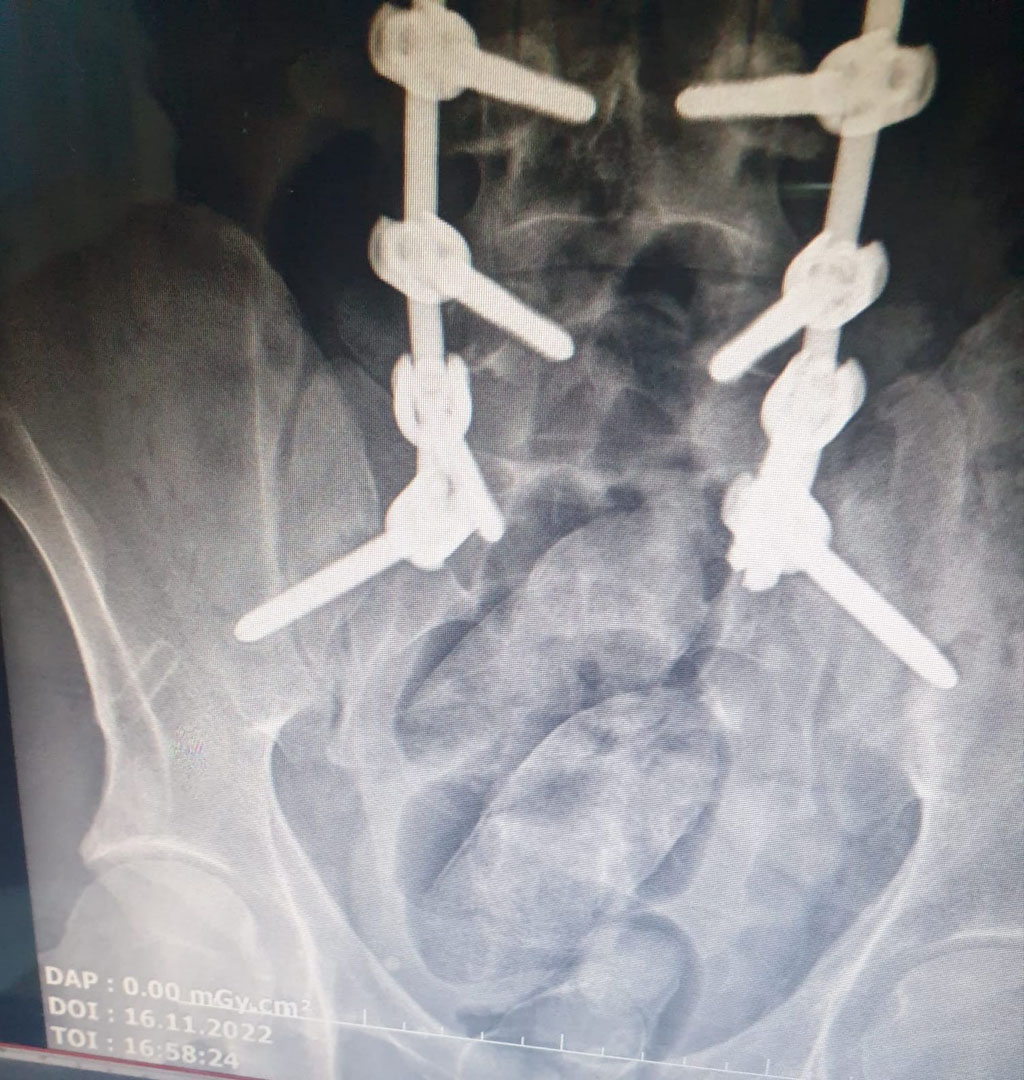

Edinilen bilgilere göre, Ağrı Narkotik Suçlarla Mücadele Şube Müdürlüğü ekipleri, İran uyruklu F.A.'nın İran'dan Doğubayazıt'a giriş yaptığını tespit etti. F.A.'yı takibe alan ekipler, şahsı ilçe sınırları içinde yakaladı. Doğubayazıt Doktor Yaşar Eryılmaz Devlet Hastanesi'nde şüphelinin yapılan sağlık kontrolünde midesinde yabancı cisimler olduğu tespit edildi.

Cisimler doğal yolla çıkartıldıktan sonra yapılan kontrolde 3 paket halinde 124,9 gram metamfetamin ve 1 paket 4,65 gram reçine esrar olduğu değerlendirilen madde ele geçirildi. "Uyuşturucu veya uyarıcı madde ticareti yapma veya sağlama" suçundan gözaltına alınan F.A., çıkarıldığı mahkemece tutuklandı.